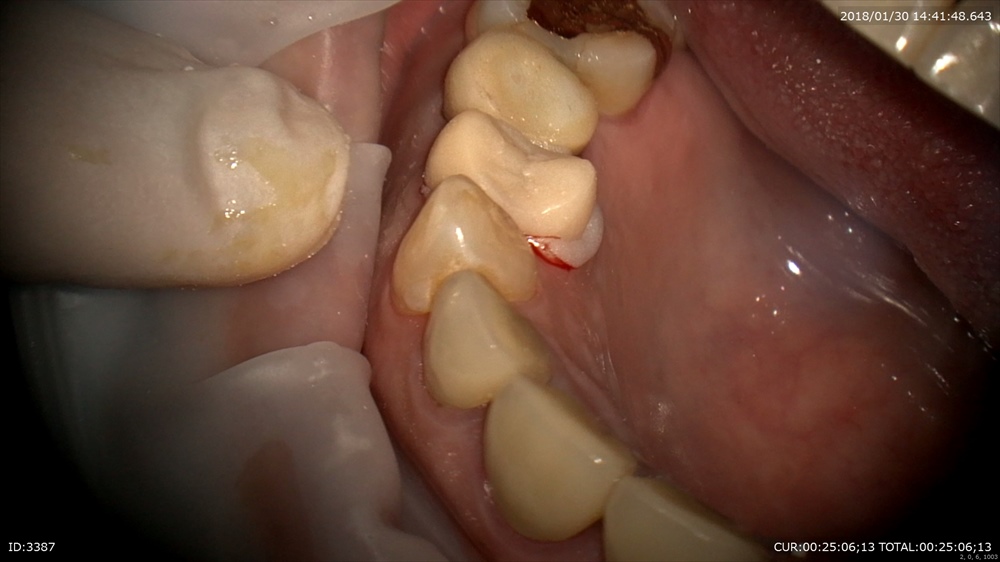

精密根管治療が終わると土台を立てます。

丁寧に削ります。

ここから仮歯を作りフィット

ガイドや形を与えます。

これで使用して問題なければ本物の型を精密に採るわけです。

だから仮歯が重要、形や大きさ、などあらゆる情報が入っています。当院で仮歯がない状態がないのはそのような理由からです。